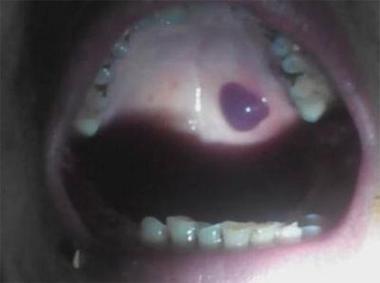

口腔内黑色血泡是何原因?

口腔内突然出现一个黑色或紫黑色的血泡,确实会让人感到紧张和不安,别担心,这种情况在口腔科非常常见,绝大多数情况下是无害的。

最可能的原因:外伤性血泡 (Traumatic Hematoma / Blood Blister)

这是最常见的原因,占了绝大多数情况。

- 成因:由于不小心咬到、烫到、或者吃到尖锐的食物(如薯片、坚果壳)划伤了口腔黏膜下的微小血管,血液从破裂的血管渗出,但被坚韧的黏膜层包裹,无法流出体外,就形成了一个充满血液的血泡。

- 颜色:通常是鲜红色、深红色或紫黑色,颜色深浅取决于出血量和出血时间,刚形成的可能偏红,时间稍长(几小时后)血液会氧化,颜色就会变深,接近黑色。

- 形状:通常是圆形或椭圆形,边界清晰。

- 感觉:初期可能感觉有异物感或轻微胀痛,有时不痛不痒,触碰时可能会有柔软的波动感。

- 位置:可以发生在口腔任何有黏膜的地方,如内侧脸颊、嘴唇内侧、舌下、上颚等。

口腔内出现黑色血泡,90%以上的可能性是单纯的外伤性血泡,对身体没有危害,通常会在1-2周内自行消退。